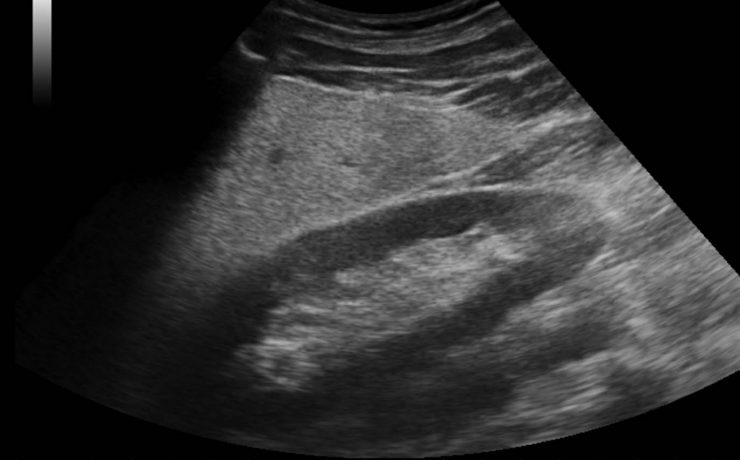

El diagnóstico de tumores ováricos durante el embarazo es cada vez más frecuente como consecuencia del mayor uso rutinario del ultrasonido desde etapas tempranas de la gestación. Si bien la frecuencia sigue siendo baja en relación con otras neoplasias asociadas al embarazo, se reporta una incidencia menor de 5%. Casi